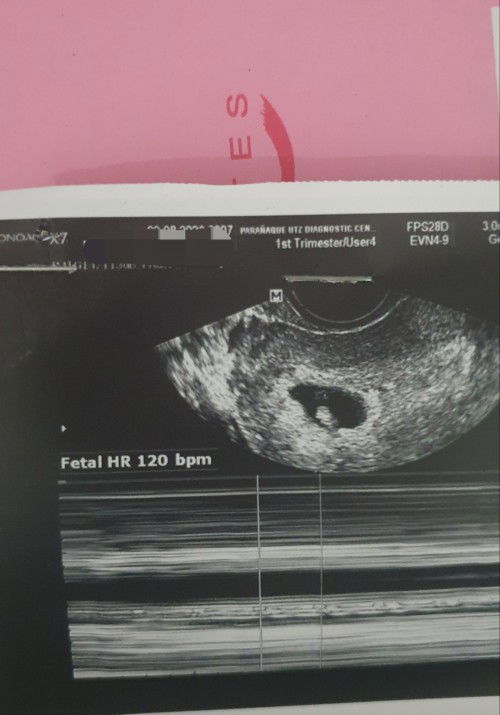

kagabi pinost ko dito yung PT na tinake ko na ang result is positive, at kanina nag decide ako na mag pa check up and mag pa transv para ma confirm kung preggy talaga ako. At confirmed nga, 6weeks and 3days preggy ako. Goodluck sakin, first time ko po eto aaminin ko na hindi pa talaga ako ready since hindi namin eto plinano kasi aksidente lang lahat ng nangyare (napunit yung protection na gamit namin) pero wala na kaming magagawa kundi tanggapin nalang kasi nandito na, hoping na maging okay lahat!🥰